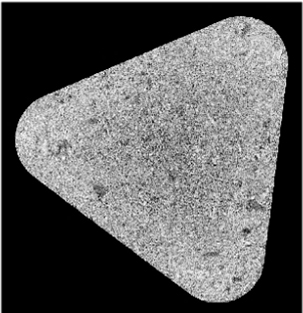

錠剤はさまざまな形状があり、作製に当たって多くのプロセスパラメータを設計する高度な技術が必要とされます。そのようにして作製された錠剤の中には、キャッピングなどのように打錠障害を有するものがあり、その原因を特定し、設計技術に生かすことが重要です。

X線CTでは、錠剤内部を3次元的に観察でき、キャッピングなどの原因となり得る空隙を確認できます。

打錠条件によって、錠剤内部に空隙が残る場合や密度分布が変化する場合があります。

X線CTでは、非破壊かつ3次元での観察により、空隙分布や密度変化の数値化が可能で、打錠条件の改善に役立てることができます。